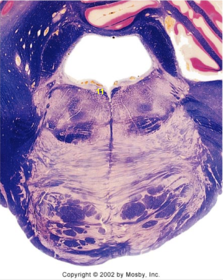

| Nucleus gracilis | |

| Accessory nucleus | |

| Medial longitudinal faciculus | |

| Pyramidal decussation | |

| Medullary pyramids | |

| Anterior spinocerebellar tract | |

| ALS | |

| Posterior spinocerebellar tract | |

| Spinal tract of V | |

| Spinal nucleus of V | |

| Nucleus cuneatus | |

| Fasciculus cuneatus | |

| Fasciculus gracilis | |

| Central canal | |